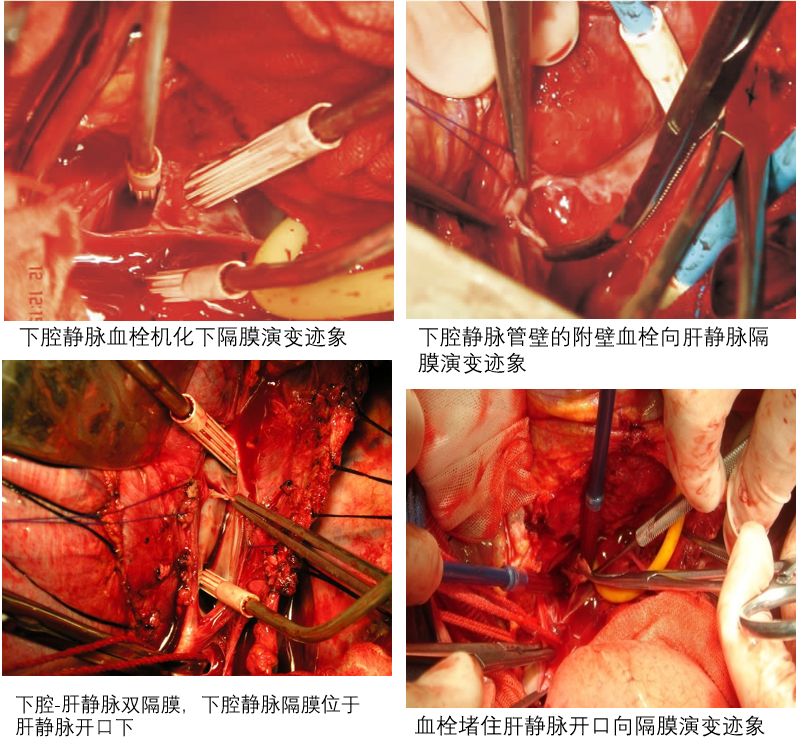

传统教科书描述下腔静脉隔膜多位于肝静脉开口上方,认为这样才能阻塞肝静脉。然而,术中直视下观察发现:

隔膜多数位于肝静脉开口下方,所谓“肝静脉阻塞”其实多为扩张的副肝静脉,真正的肝静脉开口可能并未被隔膜直接覆盖。

隔膜可以后天形成,且可存在多个(下腔静脉及肝静脉双隔膜多见)。

下腔静脉附壁血栓可阻塞肝静脉出口,形成类似隔膜的外观。

术中直接观察和病理分析带来了对BCS病因的全新认识:

观察到血栓向隔膜演变的迹象:附壁血栓逐渐机化、纤维化,最终形成隔膜。

复发病例可见新生隔膜(例如:原为下腔静脉血栓,7年后复发为隔膜)。

结论:如果隔膜是先天的,其成分应与血管壁相近;但实际与血栓高度一致,支持隔膜由血栓演变而来。

隔膜是血栓机化的终末产物:附壁血栓堵塞肝静脉出口 → 机化、纤维化、玻璃样变、钙化 → 形成隔膜。